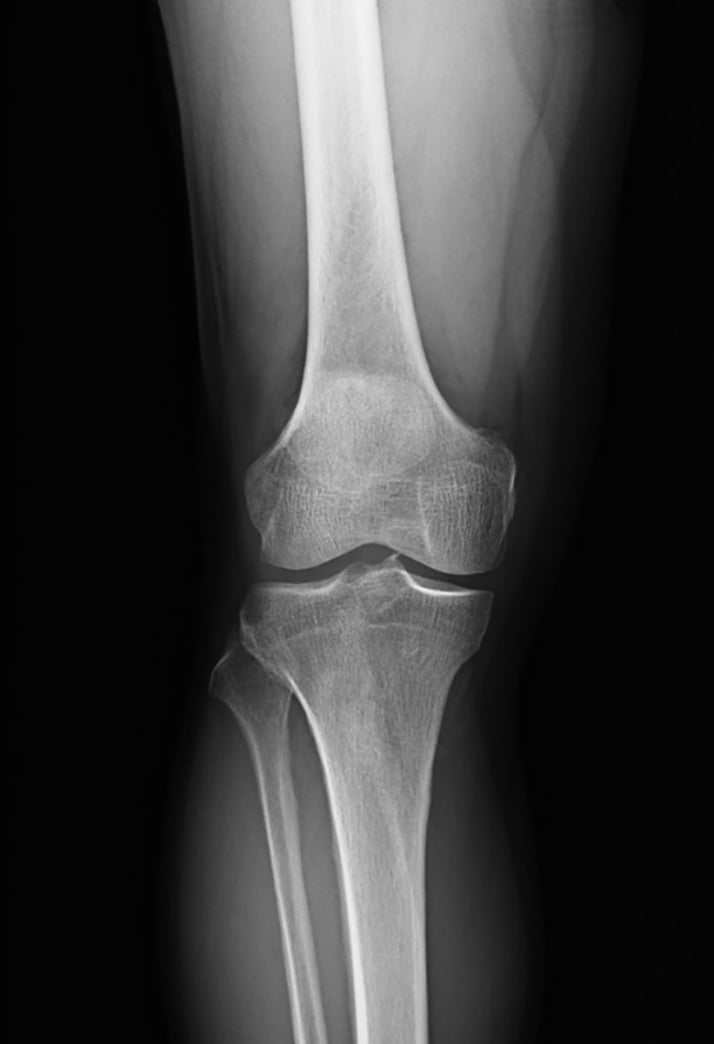

【写真を見る】健常者と「変形性膝関節症」患者のレントゲンを比較

変形性膝関節症とは、どんな病気なのでしょうか。基本的に膝関節の軟骨がすり減ってしまうことで起き、長い時間をかけて進行します。初期の特徴は、動き出しの際に痛むことです。医学的には「スターティングペイン」と呼ばれ、最初はこのような症状が年に何度か起きる。しかし、時間がたつにつれ痛む頻度が増え、安静時でも痛みが続くようになる。進行すると膝に水がたまり始め、まっすぐだった脚が曲がってきます。